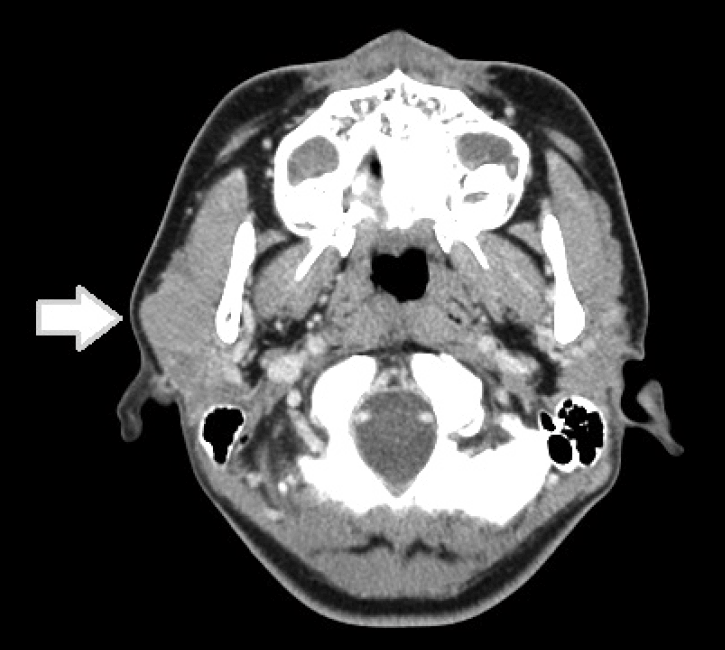

경부 전산화단층촬영상, 우측 이하선 천엽에 2.2×2.2×3.6 cm 크기의 종물이 있었으며, 종물은 둥근 형태를 띄며 가장자리가 조영 증강을 보이며 내부로는 균일하고 경계는 분명하였다(Fig. 1). 경부 초음파상 1.7×2.0×1.4 cm의 내부 혈류를 동반한 저음영의 종물 소견을 보였으며, 초음파하 세침 흡인 세포 검사를 시행하였다. 세포병리 결과상 비정형 림프 세포만 있어 확진에는 불충분한 소견을 보였다. 종양의 치료와 병리 진단을 위해 수술을 하기로 하였으며, 술전 혈액 검사를 포함하여 다른 검사상 이상 소견은 없었다.

CT scan with contrast enhancement shows a 2.2×2.2×3.6 cm sized mass (arrow) in the superficial lobe of the right parotid gland with mild enhancement.